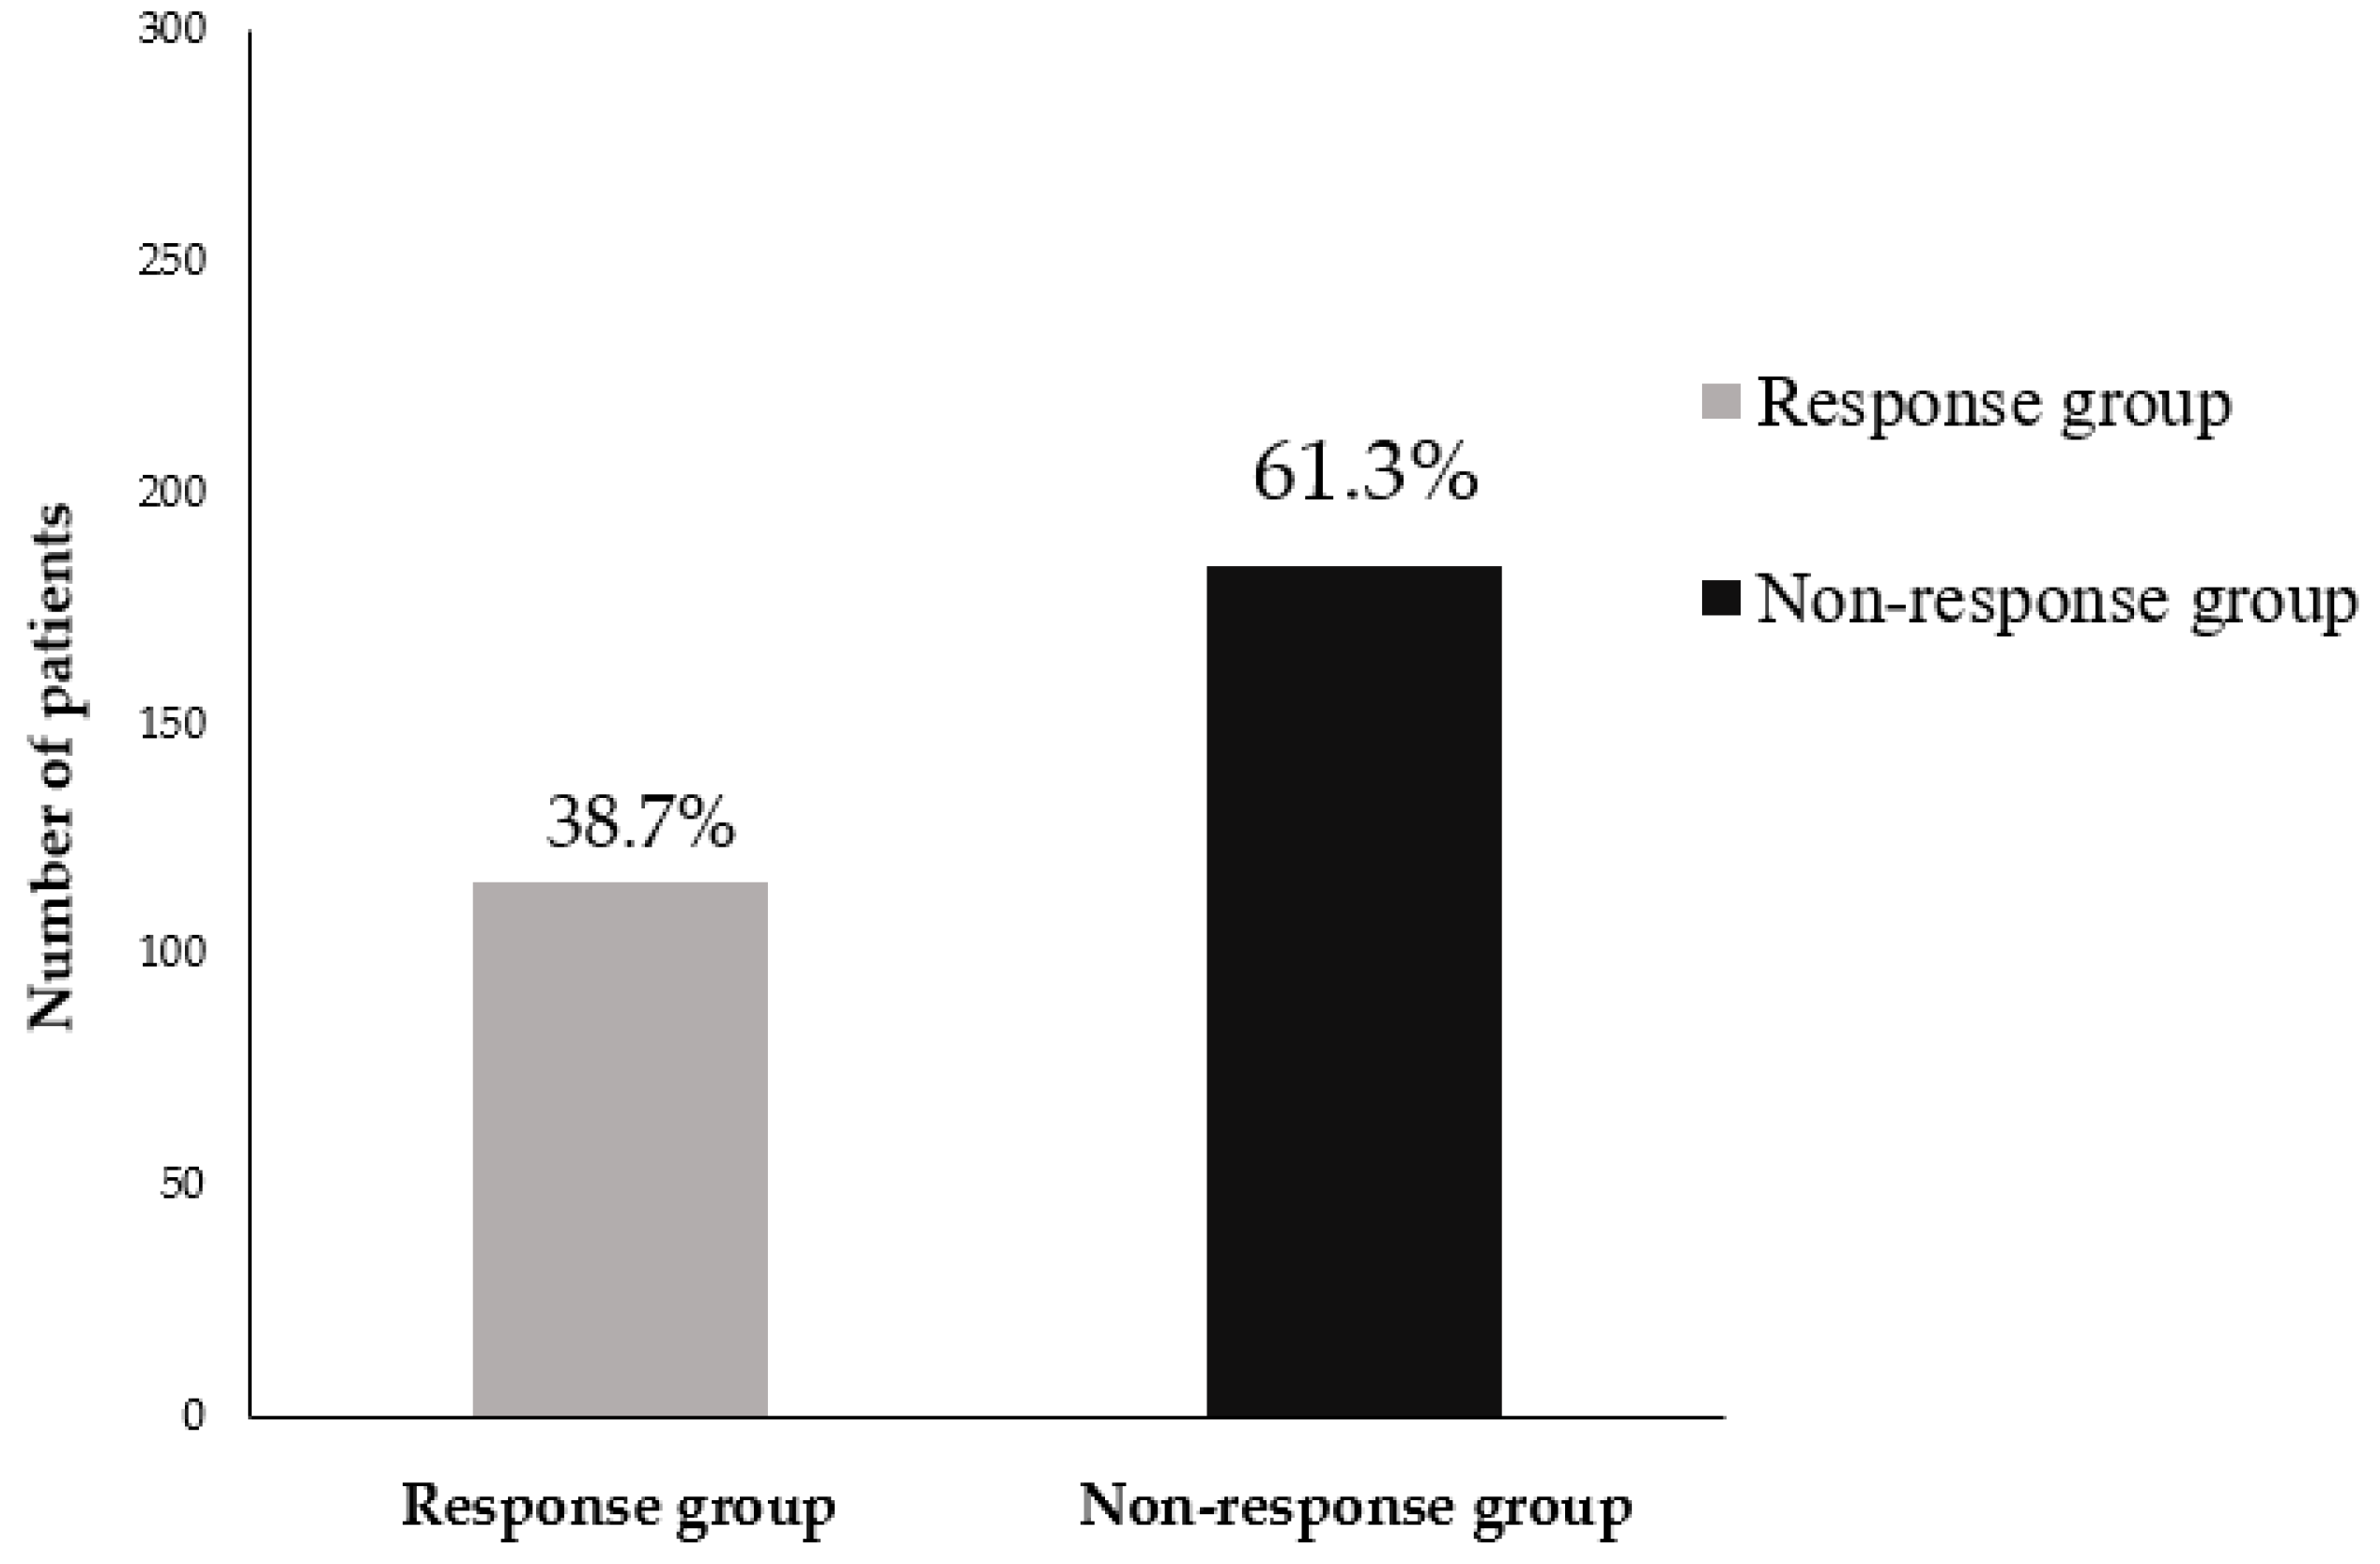

3.1. Incidence Rate of Bisphosphonate Treatment Failure